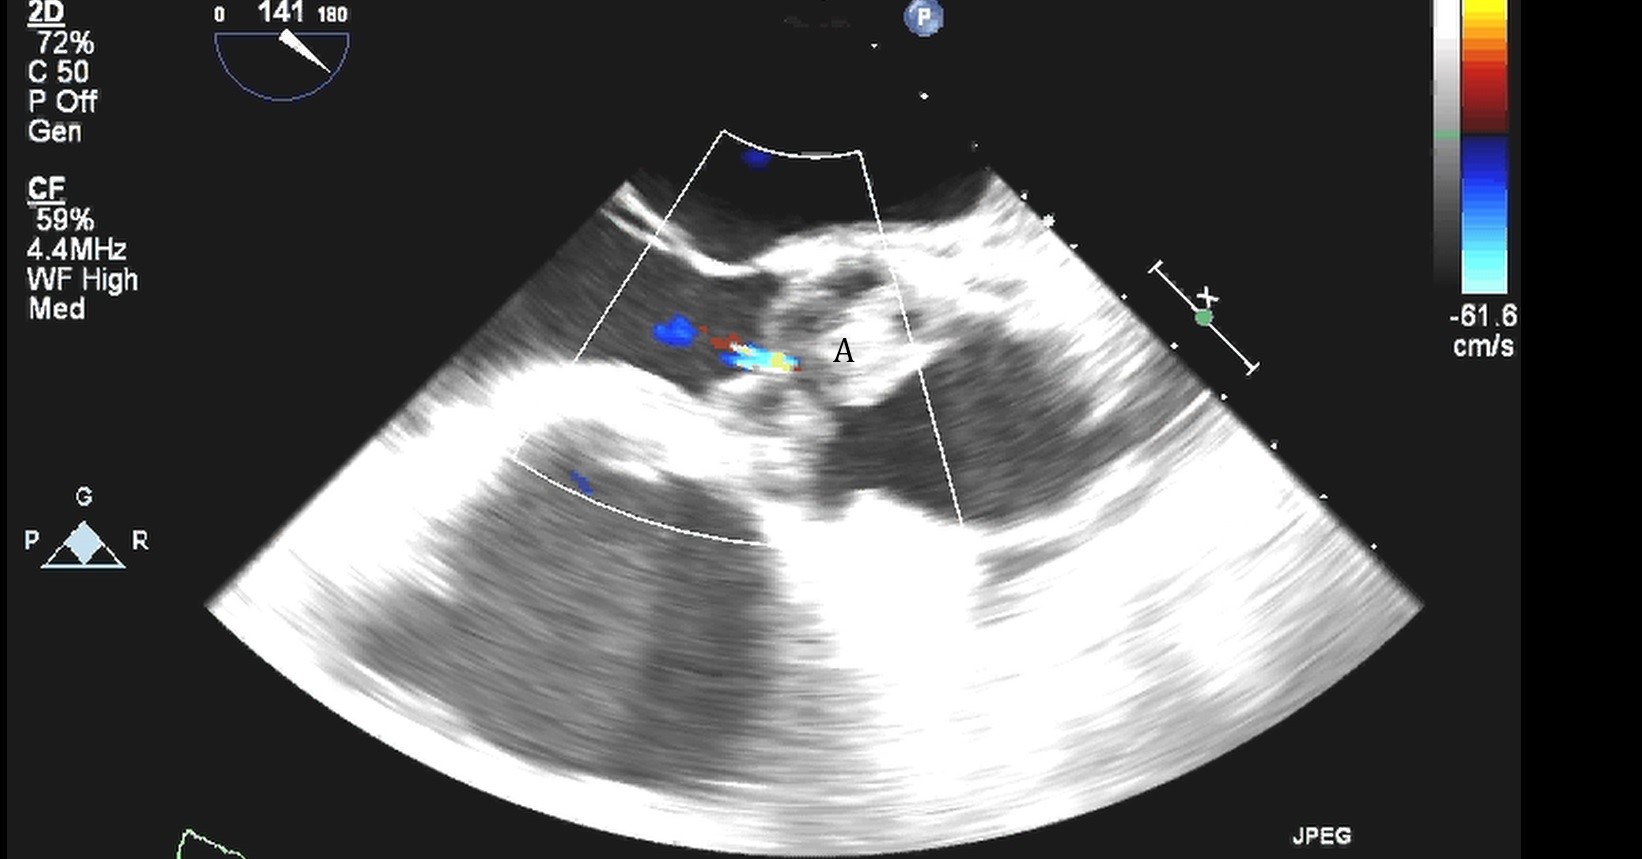

Impella (A) in the LV cavity caused disruption and damage to subvalvular apparatus resulting in flail segment (B) of the mitral valve.

Fig. 4.Impella (A) placement causing disruption and damage to subvalvular apparatus resulting in mitral valve flail (B) and mitral regurgitation (C).